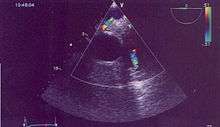

Possible communication between left coronary artery and pulmonary artery in a 45-year-old woman with Bland-White-Garland syndrome.